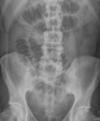

**R renal stones** (also horseshoe kidney)

General approach for AXR interpretation